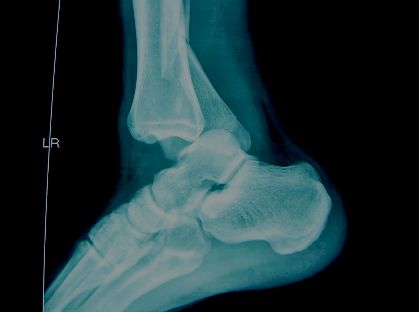

踝关节解剖

• 踝穴—由内外踝和距骨体组成,正常时内外等宽≦4mm

踝关节的韧带损伤

• X—RAY 踝关节正侧位(必要时应加照踝穴位)

应力位片